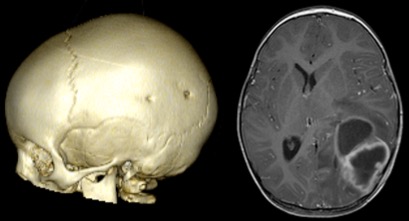

morsure par grand chien (dogue allemand) ; un mois plus tard, l’enfant présente un abcès cérébral grave avec ventriculite - lésions de l’étage antérieur